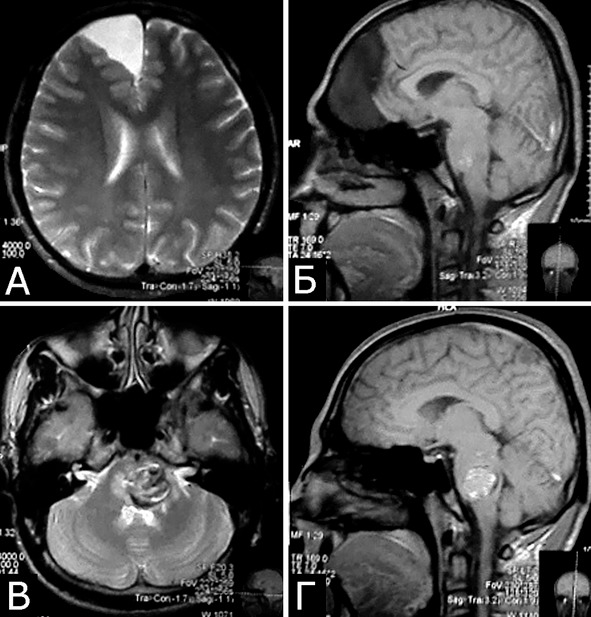

Рис. 2. Б-ной П, 22 г. Сочетанная сосудистая патология мозга: Множественные КМ головного мозга. Аномалия развития венозной системы мозга. А – КМ височной, теменной и затылочной долей слева (МРТ, режим Т2, аксиальная проекция). Б, В – аномалия развития костей и оболочек мозга в виде локальной деформации внутренней костной пластинки и губчатого вещества теменных костей в области впадения патологической вены в ВСС. Расщепление аномального ВСС на две лакуны, пролабирование мозга в область дефекта (МРТ, режим Т1, сагиттальная и фронтальная проекции). Г – аномалия венозной системы в виде отсутствия прямого синуса, формирования крупной патологической вены, впадающей в заднюю треть ВСС (МРТ-АГ, сагиттальная проекция)

1. Опухоль (менингиома) мосто-мозжечкового угла справа (А – МРТ с введением КВ, режим Т1, аксиальная проекция, Б – МРТ, режим Т2, сагиттальная проекция); 2. КМ верхнее-медиальных отделов левой гемисферы мозжечка (В, Д – МРТ, режим Т1, аксиальная проекция, Г, Е – МРТ, режим Т2, сагиттальная проекция. Стрелкой указана дополнительная тень гиперинтенсивного сигнала – косвенный признак венозной ангиомы). 3. Венозная ангиома (стрелки) левой гемисферы мозжечка (Ж, З – прямая АГ, венозная фаза). Клиническое течение: в течение нескольких лет – сильные стреляющие и ноющие боли в левой половине лица и головы

Рис. 5. Б-ной Е-ов, 30 лет. Сочетанная патология мозга: Большая арахноидальная киста правой лобной области, неуточненной этиологии (А, Б – МРТ, режимы Т2 и Т1, аксиальная и сагиттальная проекции). Крупная КМ ствола мозга на уровне средней и нижней трети варолиева моста, больше слева (В, Г – МРТ, режимы Т2 и Т1, аксиальная и сагиттальная проекции). Клиническое течение: острое развитие левостороннего гемипареза с последующим частичным регрессом